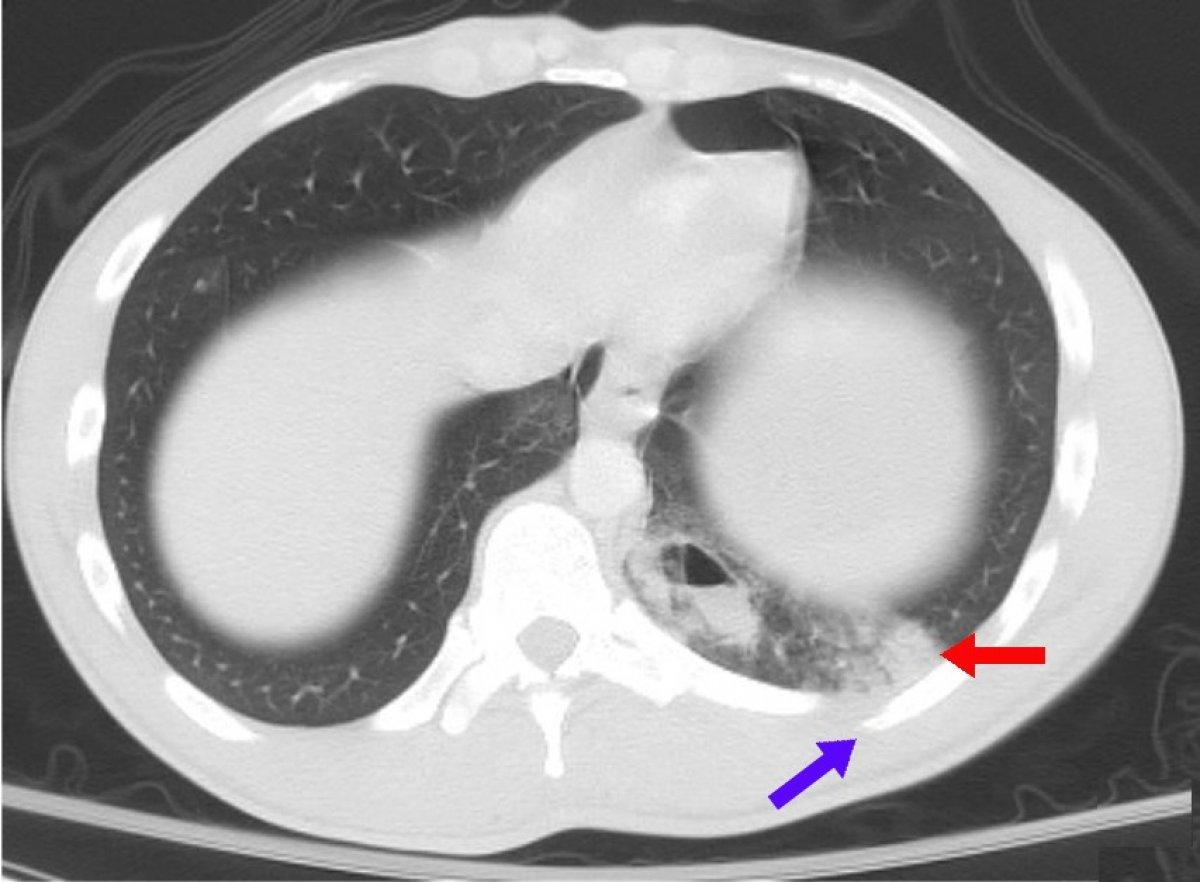

Asemptomatik olgularda hasta medikal testlere tabi tutulmazsa, hastalık ortaya çıkmaz (X-ray ve diğer tetkikler). Bazı kanserli hastalar uzun bir süre asemptomatik kalabilirler, böyle hastalarda ihtiyati önlemler alınmalıdır.